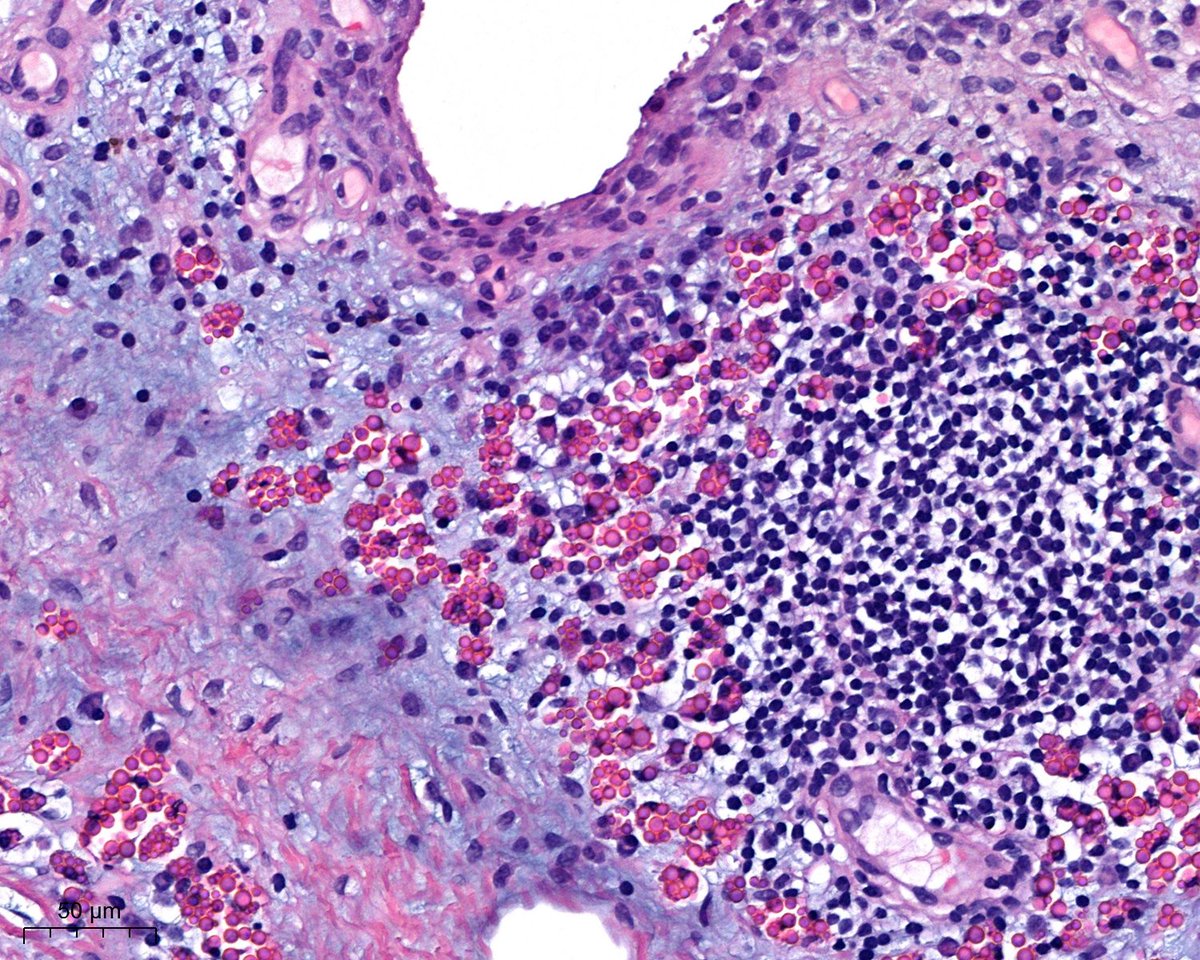

What is this? - easy; Where are we? - difficult? 😃Dr. Luca Olaleke Folaranmi Tania Labiano Aurélien Morini, MD, MSc 🇫🇷🇪🇺💙💛 Celina Stayerman MD 🔻Nusrat Zahra🔻🇵🇸 @miss_me1986 Gonzalo De Toro Tristan Rutland MBBS FRCPA IFCAP GI James Anandi Lobo, MD Angel Panizo MD, PhD 🇪🇸 🔬 Sumanta Das Lorand Kis Laura G. Pastrián MD Carlos Miguel Ruiz Carlos Nieves

benign nodule of the breast😃#breastpath Dr. Luca Olaleke Folaranmi Alexander Damron, MD Liza Quintana, MD Anne Grabenstetter Tania Labiano Jenny Pincus, MD Aurélien Morini, MD, MSc 🇫🇷🇪🇺💙💛 Celina Stayerman MD 🔻Nusrat Zahra🔻🇵🇸 @miss_me1986 Gonzalo De Toro Tristan Rutland MBBS FRCPA IFCAP Sumanta Das Israh Akhtar Khan Lorand Kis Carlos Miguel Ruiz Carlos Nieves